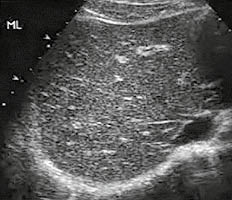

Візуалізується помірне збільшення печінки, краніокаудальний розмір правої частки становить 162 мм (в нормі — 140-150 мм), краніокаудальний розмір лівої частки — 106 мм (в нормі — 80-100 мм). Передній край помірно заокруглений. Ехоструктура органа помірно неоднорідна внаслідок дрібних дифузно розташованих гіперехогенних включень. Наявна гіперехогенність стінок дистальних гілок ворітної вени (рис. 5).